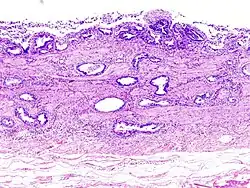

Invasão linfática de adenocarcinoma na vesícula biliar capturada numa histopatologia -

Histopatologia de um adenocarcinoma da vesícula -